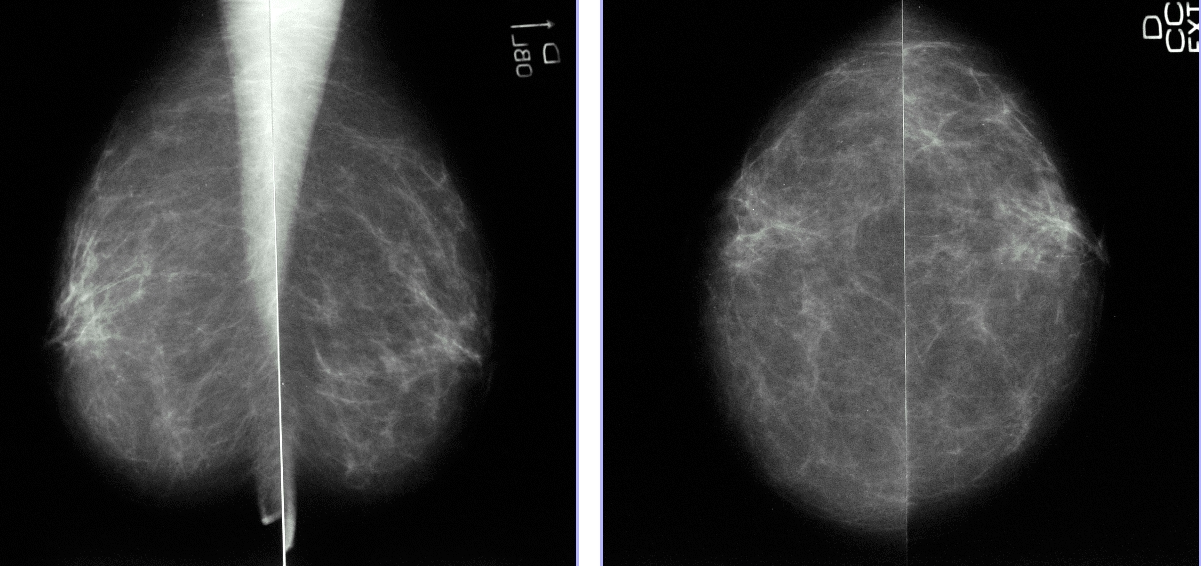

Родинка на груди при маммографии - фото презентация